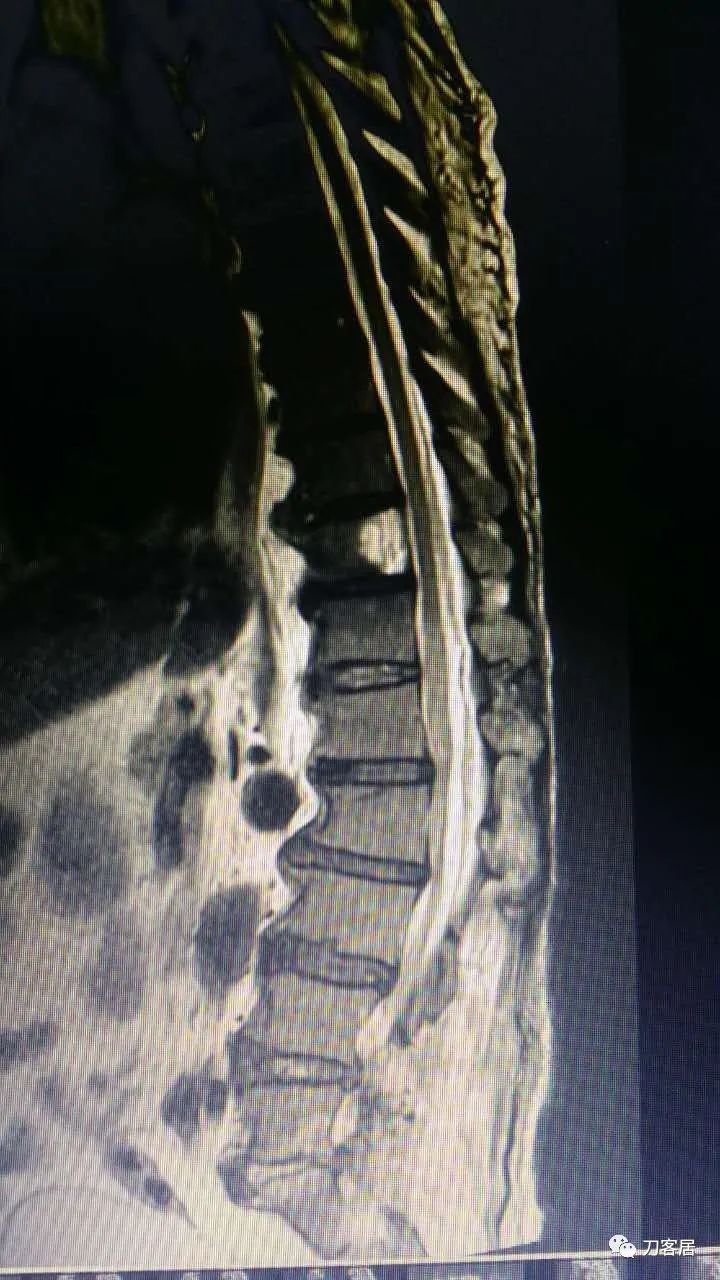

这个患者是我们西京医院骨科一位老教授在福建老家的哥哥,2015年8月份,他因为腰椎间盘突出症到福建泉州东南医院找黄约嘉主任做手术。手术很顺利,术后发生腰1-2和胸9-10椎管内血肿,手术平面以上两处椎管内血肿,当时他咨询我,我建议直接打开,切口向上延伸,清理血肿。我们科的老教授给他建议,两处血肿,用两个切口打开,进行血肿清理。最后他问我,是否可以穿刺抽吸血肿,我如实给他说,我自己没做过,但理论上是可以的,因为只要血肿没有凝固,是可以抽吸出来的。他当时晚上一直在纠结,本来想请麻醉医生帮忙穿刺,麻醉科医生没把握,后来是黄约嘉主任自己在CT引导下两处穿刺把血肿抽吸出来后患者症状缓解,血肿治愈。

术后第二天拔出引流管,术后第四天出现右下肢酸胀,夜间即使使用安定,也不能入睡,然后向我咨询,并做进一步检查,发现是椎管内血肿,血肿范围有两处,一处是胸9-10,另一处是腰1-2椎管内,最后,在两个部位进行穿刺,胸9-10平面穿刺,抽吸出4ml积血,腰1-2平面穿刺抽吸出6ml积血,血肿抽吸引流后治愈。

加注图4. 2015年8月17日术后5天,复查腰椎MRI提示术后改变,此平面图并没有见椎管内异常改变。

加注图5. 2015年8月17日术后5天,复查腰椎MRI提示术后改变,此平面图现在看,似乎在腰1-3椎管后方有异常信号改变,但当时手机上看,咨询我的时候,我并没有看出来,这是在电脑上操作,放大图看,似乎这里还是有问题的,但腰4-5,腰5骶1平面,椎管内信号紊乱,应该是手术后的正常表现。

加注图6-加注图7. 腰4-5、腰5骶1平面,可见手术入路形成的减压窗口。椎管内无血肿压迫。